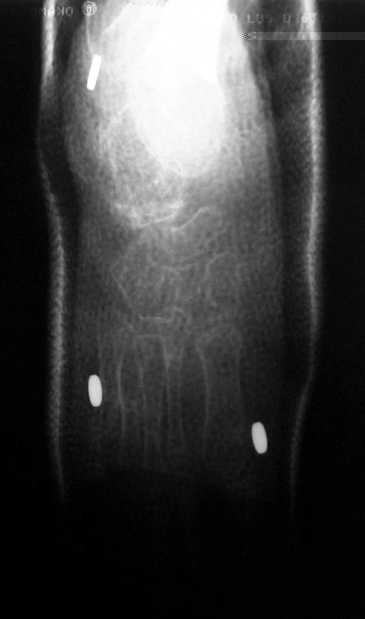

Case 1